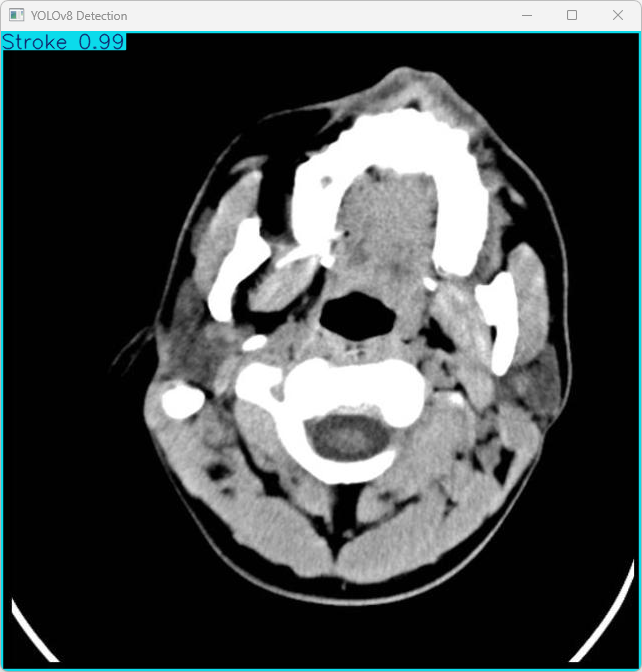

执行imgTest.py代码后,会将执行的结果直接标注在图片上,结果如下:

利用YOLOv8模型对文件名为imagetest.jpg的图片进行检测的输出结果如下:

图像信息:

(1)处理的图像路径为:TestFiles/imagetest.jpg。

(2)图像尺寸为640×640像素。

检测结果:检测到 1 个 Stroke(中风)

处理速度:

(1)预处理时间: 5.0 毫秒

(2)推理时间: 9.0 毫秒

(3)后处理时间: 73.8 毫秒

总结如下:

系统能够正确识别出图像中的脑卒中相关特征(CVA),其完成时间为 87.8ms(约需 0.0878 秒),完全满足快速检测的要求。检测结果已可靠地保存在指定目录中,并将为后续的验证工作以及实际应用提供便利条件。